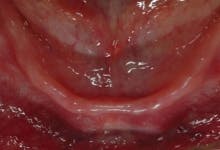

The ScrewIndirect one-piece implant offers a 3.0 mm D implant with adequate strength. All four diameter options (3.0 mm, 3.7 mm, 4.7 mm and 5.7 mm) have the same 5 mm D multi-unit platform. The 3.0 mm D implant allows treatment of narrow ridges and simplifies accurate placement during flapless surgery. Providing teeth in one day to edentulous patients and immediate implant placement following extractions is becoming the treatment of choice. The patient's existing denture is converted to a fixed-detachable prosthesis immediately following implant placement. This is accomplished by attaching titanium sleeves to the implants that project through holes cut in the denture and attached them to the denture with cold-cure acrylic followed by shortening the denture flanges.